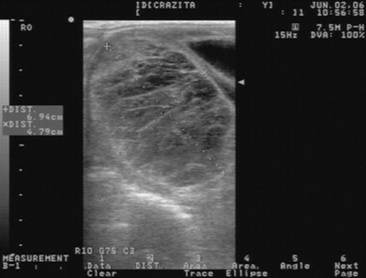

Ovulation failure is a normal physiologic event for the mare during the spring and fall transition periods, but it may also occur occasionally during the physiologic breeding season. Persistent anovulatory follicles (PAFs) may be quite large (5 to 15 cm in diameter), persist for up to 2 months, and result in abnormal estrous behavior and prolonged interovulatory intervals.89 The cause of ovulation failure has been suggested to be endocrine in nature. Absence of sufficient pituitary gonadotropin stimulation to induce ovulation, or insufficient estrogen production from the follicle, has been proposed as a possible mechanism. PAFs were reported in a recent study to occur in approximately 8.2% of estrous cycles.67 The formation of an anovulatory follicle was preceded by development of normal endometrial folds or edema in 78.3% of these cases. Initial growth patterns of follicles destined to become anovulatory were usually normal, and the first indication of a problem was the detection of echogenic particles within the follicular fluid. The incidence of PAFs was also found to increase with age.

PAFs may contain blood and have been termed hemorrhagic anovulatory follicles., The hemorrhage can be detected ultrasonically as scattered free-floating echogenic spots within the follicular fluid. The follicular fluid may form a gelatinous, hemorrhagic mass within the follicular lumen. Ultrasonographically these structures may contain echogenic fibrous bands traversing the follicular lumen (Fig. 43-5). A thickening of the follicular wall may be observed in anovulatory follicles. This thickening is often associated with luteinization of the follicular wall, and 85.7% of PAFs were found to be luteal structures based on elevations in plasma progesterone concentrations.67

image

Fig. 43-5 Transrectal ultrasonographic image of a persistent anovulatory follicle in a mare.